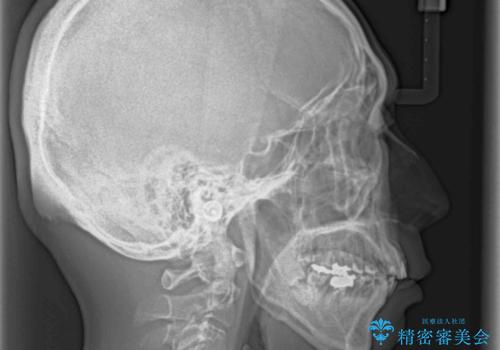

- 八重歯を気にして来院された患者様です。

上顎前歯の突出感と右上の八重歯を気にされていたので、上顎左右の第一小臼歯2本を抜歯し、ワイヤー装置にて矯正治療を行うこととしました。